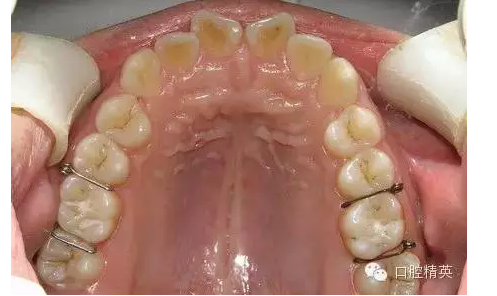

圖6 【臨床應(yīng)用要點(diǎn)】

◆雖然目前正畸臨床上醫(yī)生多用彈力橡皮圈分牙,但當(dāng)?shù)诙パ雷枭c第一磨牙鄰接不良時(shí),或成人第一、第二磨牙鄰接太緊密時(shí)以及牙鄰面為面狀接觸的兩鄰牙者,則分牙簧是唯一能解決分牙問(wèn)題的有效方法;正畸醫(yī)生應(yīng)作為后備技術(shù)熟練掌握其應(yīng)用技巧。

◆分牙簧各個(gè)口腔醫(yī)療器材商都有成品供應(yīng),但基本上是圖1形狀,即未激活狀態(tài),正確的使用方法是:在操作前用細(xì)絲鉗夾住簧圈處齦臂向內(nèi)彎折,使齦臂末端靠近合臂,形成角度(圖2),分牙時(shí)撐開(kāi),插入鄰牙間,利用兩臂的剪切彈力,產(chǎn)生間隙。